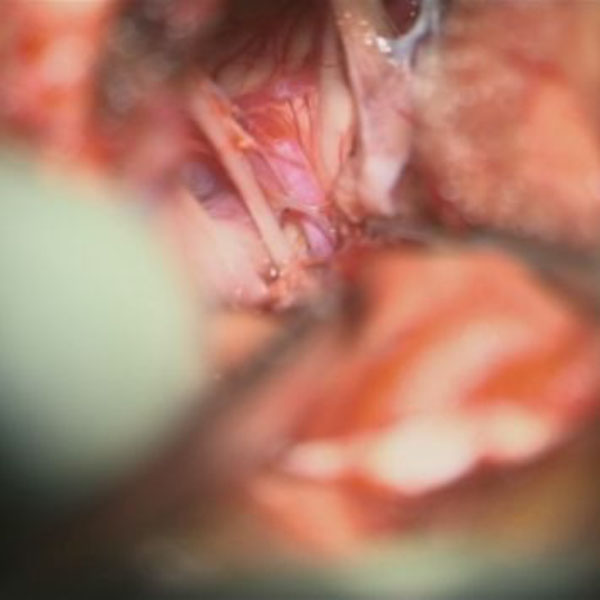

手術中

処置前